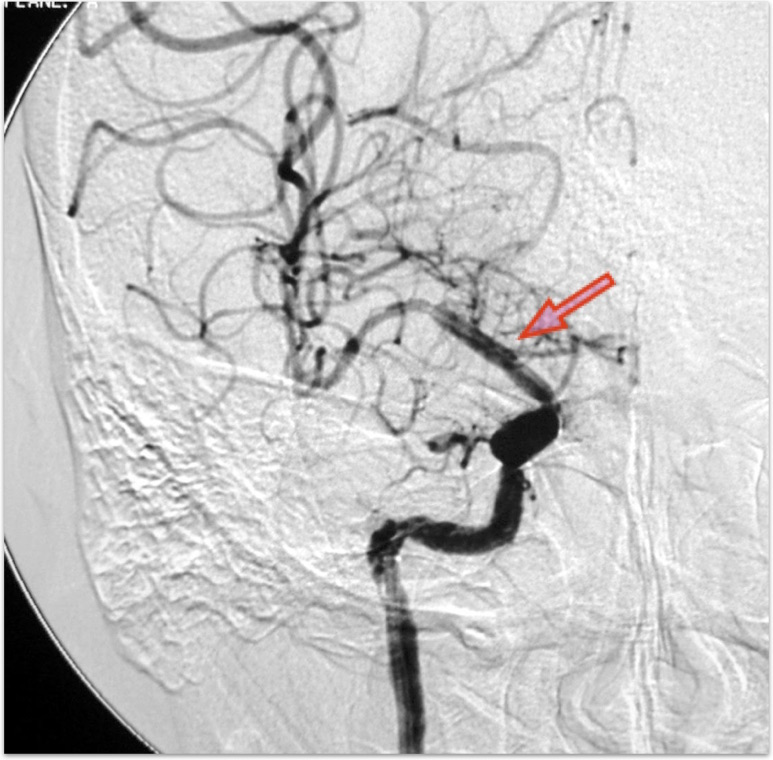

<クリッピング前>矢印は動脈瘤

<クリッピンング後>矢印はクリップ